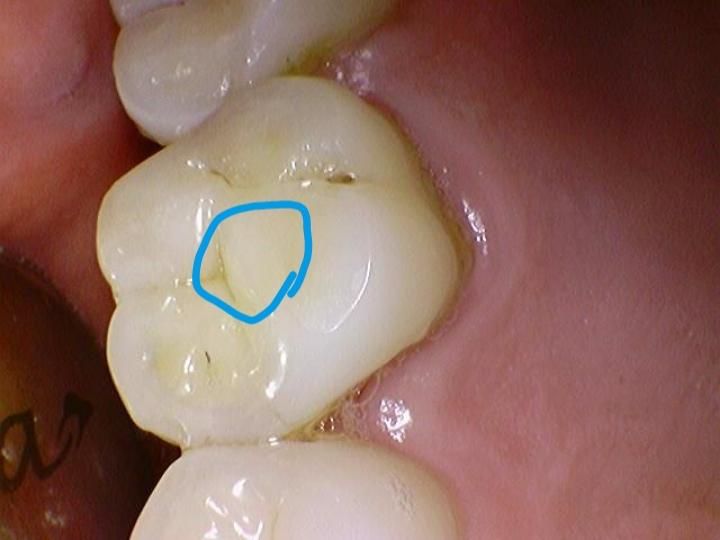

어금니 위 두번째 치아 교두부 부위가 좀 특이한 데요.치아가 약간 가로로 길죽한데다가 절구 역활을하는 교두부가 치아면 중앙에 둥그렇게 나와 있습니다.바로 아래 치아도 운석이 떨어진 자국처럼둥그렇게 패여 있구요.여기서는 사진을 올릴수가 없게 되있는거 같아서 못올리는데요. 크라운보철 할때 원래 치아 모양이 안나온다고 하던데요. 원래 모양이 안나와도 문제가 안되나요?

위아래 치아 모두 교모가 된 것인데요. 아래에 맞닿는 치아의 모양과 치아 기존의 모양을 토대로 크라운을 제작하다보니 해부학적 형태가 뚜렷하지는 않을수도 있습니다. 이럴 경우 크게 문제는 없습니다.